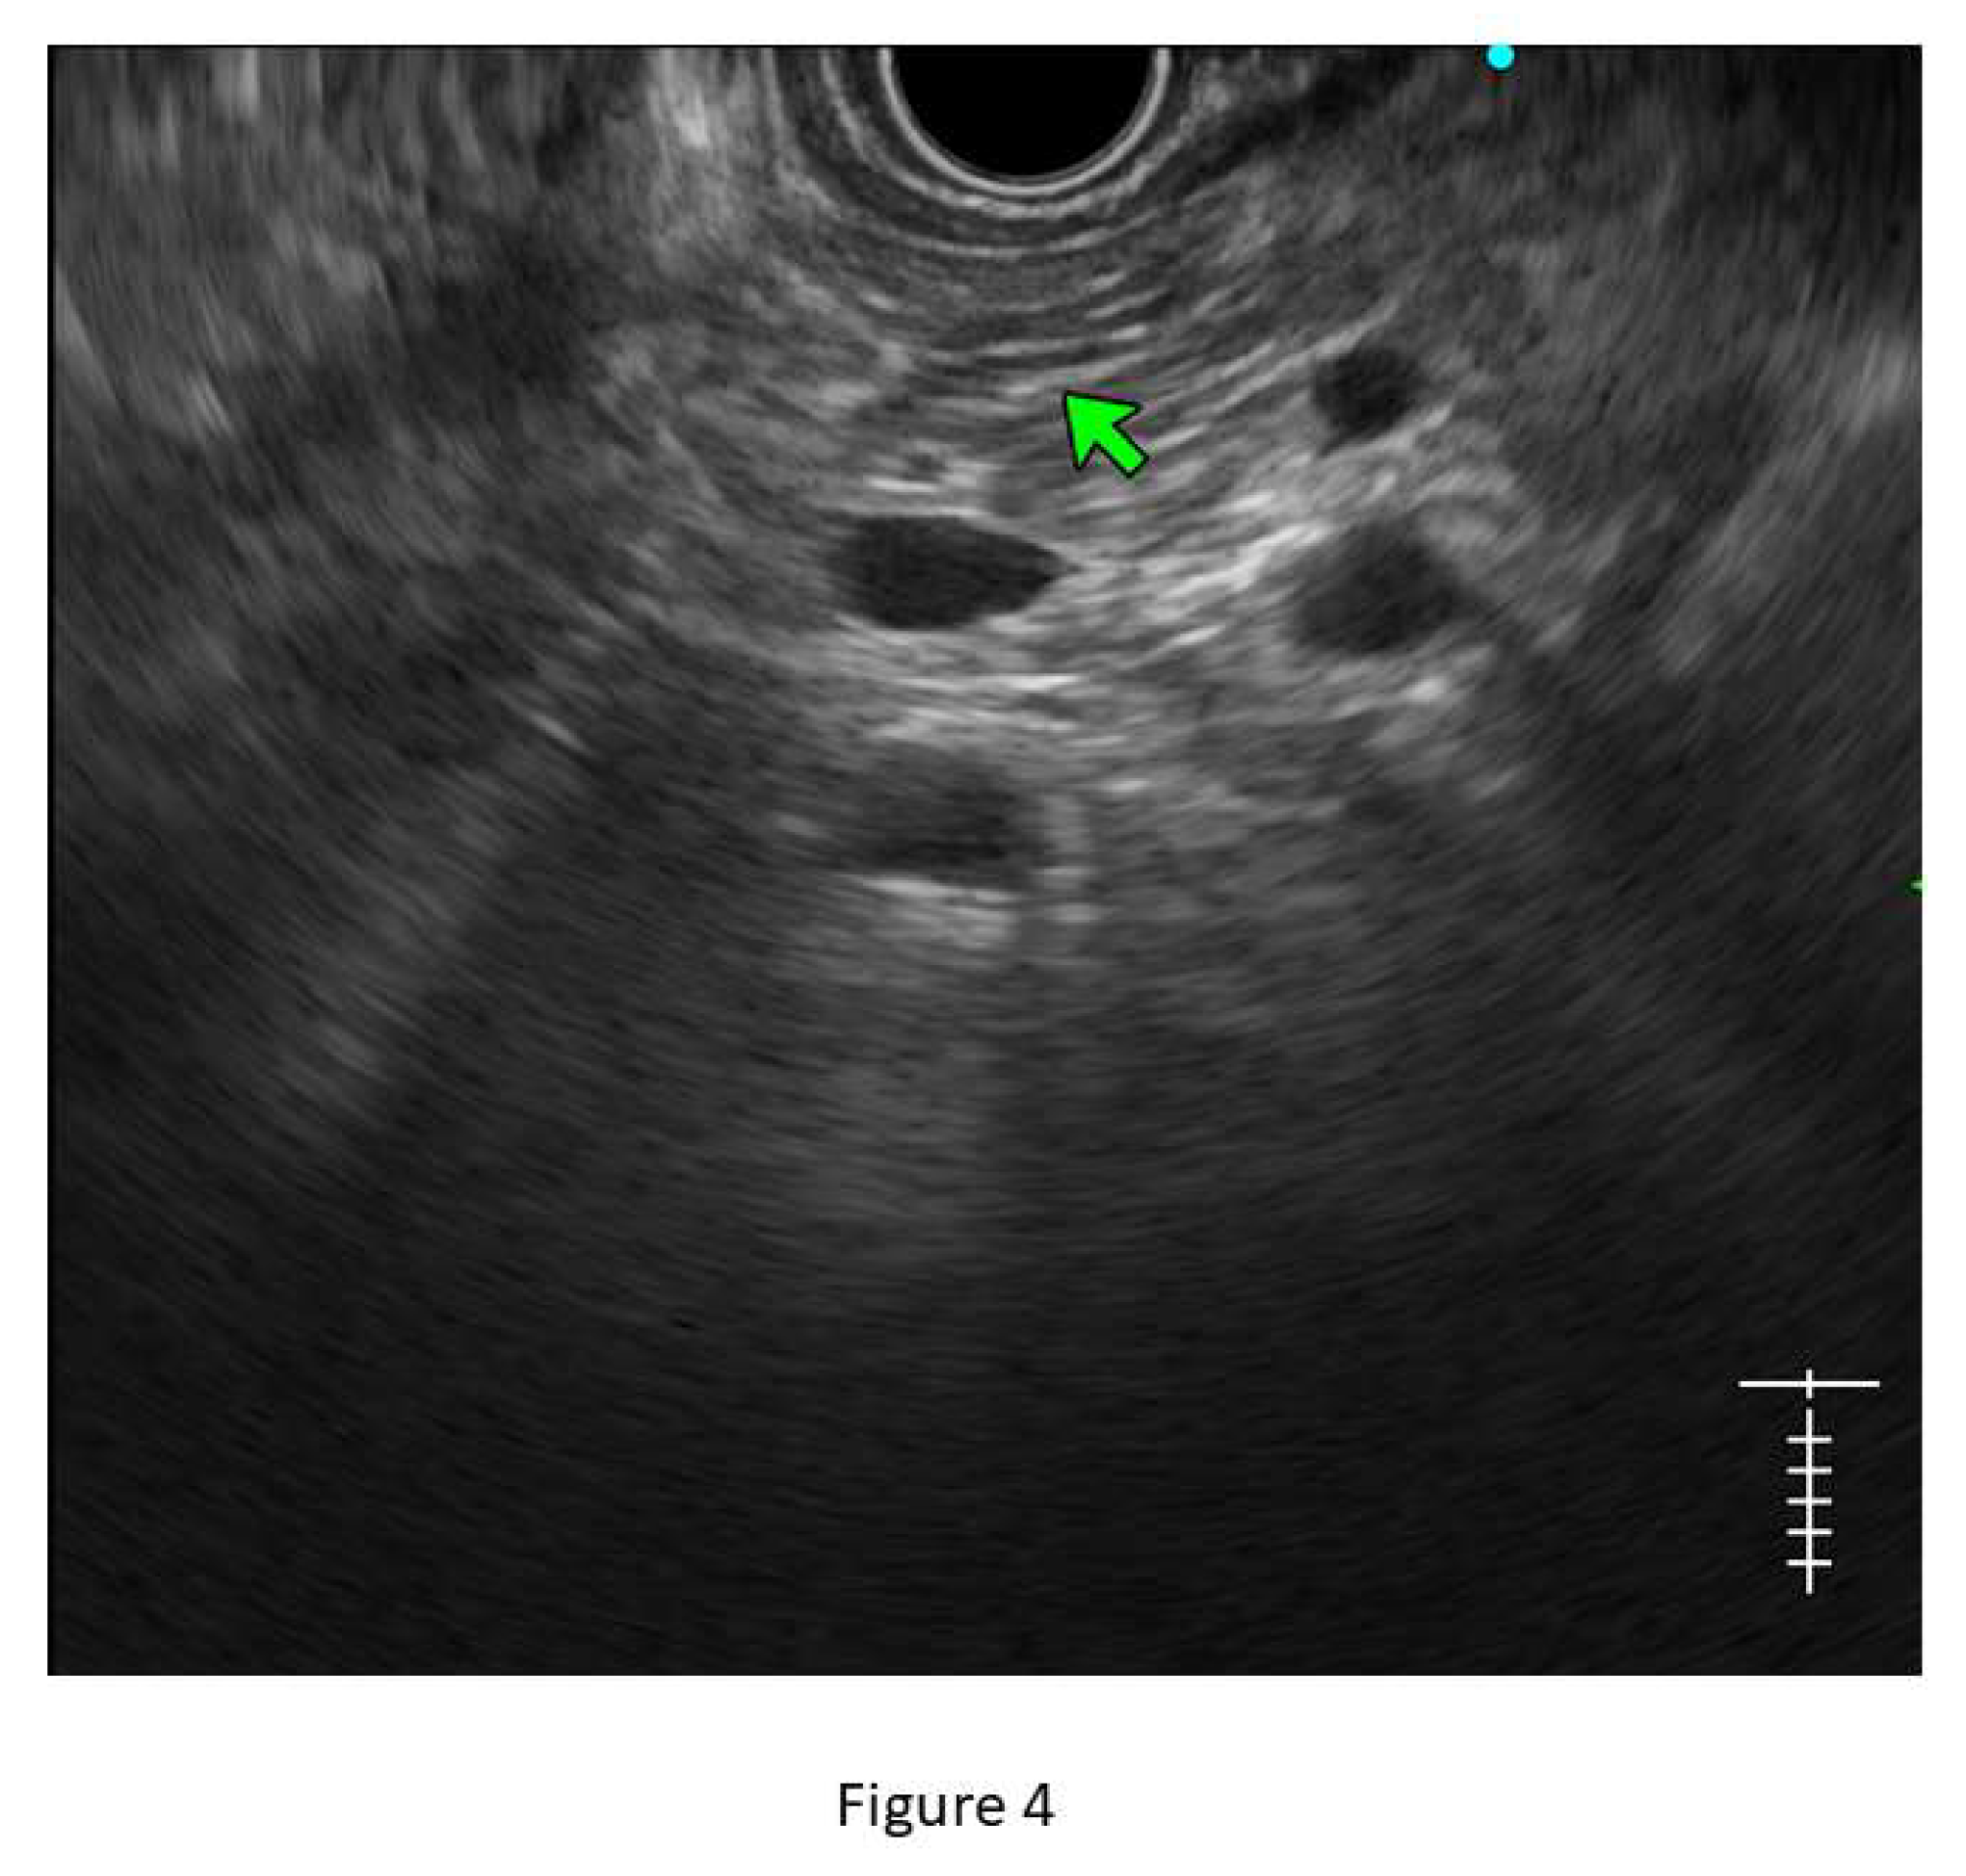

Figure 4. Showing hyperechoic stranding in different planes of images.

• Stranding: The presence of hyperechoic lines of ≥3 mm length in a minimum of two directions concerning the plane of imaging is described as ‘stranding’ in JPS criteria (in standard criteria, it is described as hyperechoic foci with stranding). Abnormal stranding is described when at least 3 such lines are noted. Stranding corresponds to bridging parenchymal fibrosis in histopathology. (Figure 4)